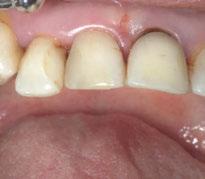

A partir del estudio radiológico y de las imágenes fotográficas podemos observar edentulismo de 17, 15, 14, 12,

Figura 1a. Foto intraoral frontal inicial.

Figura 1b. Foto intraoral lateral izquierda inicial.

Figura 1c. Foto intraoral lateral derecha inicial.

25, 26, 28, 37, 38, 47 y 48. Presentaba corona desajustada en 13 con extensión en 12, implantes en 35-36, 45-46, con coronas ferulizadas en 35-36, 45-46, y dientes anteriores superiores con enfermedad periodontal Grado IV.